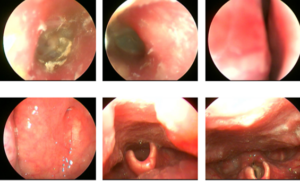

Ca lâm sàng Bệnh nhân mắc hai ung thư nguyên phát: Ung thư phổi không tế bào nhỏ và Ung thư trực tràng GS.TS. Mai Trọng Khoa, PGS.TS.Phạm Cẩm Phương, BSCKII. Lê Viết Nam, BSNT. Nguyễn Bảo Linh Trung tâm Y học hạt nhân và Ung bướu, Bệnh viện Bạch Mai Mở...